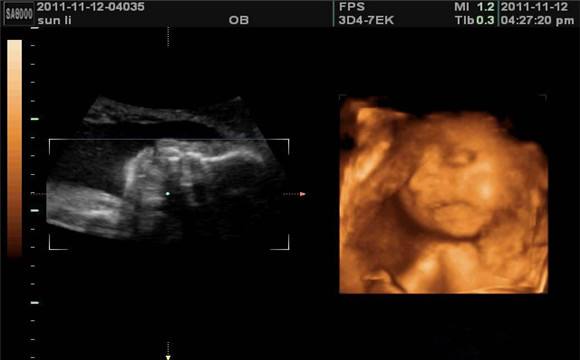

胎儿的变化

28周的胎儿现在坐高约26厘米,体重约1200克左右,这时的宝宝几乎占满了整个子宫,随着空间越来越小,胎动也在减弱。尽管胎儿现在肺叶还没有发育完成,可如果万一发生早产,胎儿在器械帮助下也可以进行呼吸。